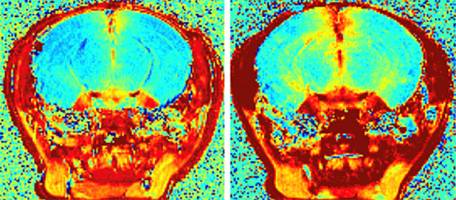

Psychologie - Droit - 18.10.2020

Les mauvaises attitudes suscitent des jugements moraux issus de nos mécanismes de survie fondamentaux. Des scientifiques de l'Université de Genève démontrent qu'ils sont liés à la puanteur. Partie du cerveau humain contribuant le plus à la prédiction de la douleur (aires oranges à gauche) et du dégoût olfactive (petites aires bleues à droite).